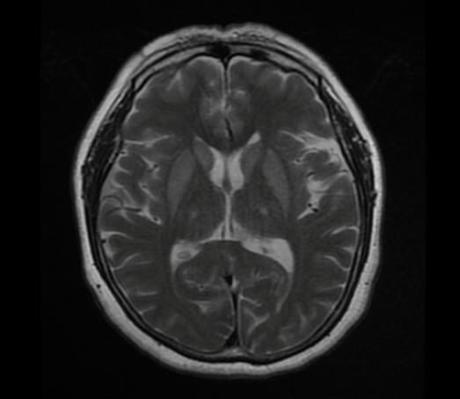

Cambios en la señal de los ganglios basales y la protuberancia, hiperintensas en Flair y con restricción en DW. Sugieren mielinolisis pontina o también llamado sind. De desmielinización osmótica, que buen caso, gracias por las imágenes

Cambios en la señal de los ganglios basales y la protuberancia, hiperintensas en Flair y con restricción en DW. Sugieren mielinolisis pontina o también llamado sind. De desmielinización osmótica, que buen caso, gracias por las imágenes

Síndrome de desmielinización osmótica con hallazgos pontinos y extrapontinos

Síndrome de desmielinización osmótica con hallazgos pontinos y extrapontinos

Mielinolisis pontina y extrapontina!

Mielinolisis pontina y extrapontina!